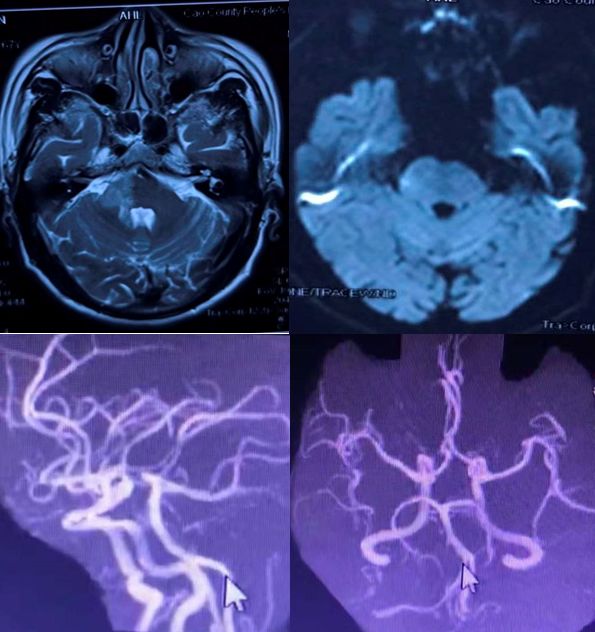

病例6

男性,67岁,因言语不清、走路不稳1天入院。既往有脑梗死和糖尿病病史,不规律服用二甲双胍,血糖控制欠佳。查体:不完全运动性失语,左侧鼻唇沟浅,口角右歪,伸舌稍偏左。余查体阴性。

增强MRI如下:

答案:肺癌脑转移

患者老年男性,多个卒中危险因素,出现卒中样症状。头MRI可见右侧桥脑小脑角区病变,DWI未见高信号,增强显示软脑膜强化,高度提示感染和肿瘤。好多老师考虑CLIPPERS,CLIPPERS多是双侧病灶,患者病灶分布于中脑、小脑及丘脑,增强表现为脑桥血管周围呈“胡椒粉”样斑点状强化病灶,部分强化病灶以脑桥为中心,随着距脑桥距离的增加,相邻病灶的数量逐渐减少,范围也逐渐缩小。